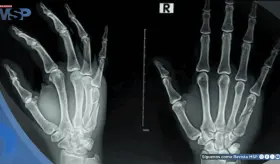

#InfografíaMSP La artrosis desgasta el cartílago que recubre las articulaciones, afectando su movilidad y provocando dolor, rigidez e inflamación. A medida que avanza, puede alterar por completo la estructura de zonas como rodillas, caderas, columna y manos.